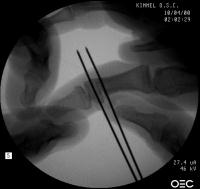

Intraoperative fluoroscopy. The mass:

Click for larger image

Osteotomy planning: proximal pin parallel to the proximal joint line, distal pin parallel to the distal joint line:

Pins were used as saw blade alignment guides:

Osteotomy closed:

Intraosseous wire passed through pin tracts, interfragmentary pin: